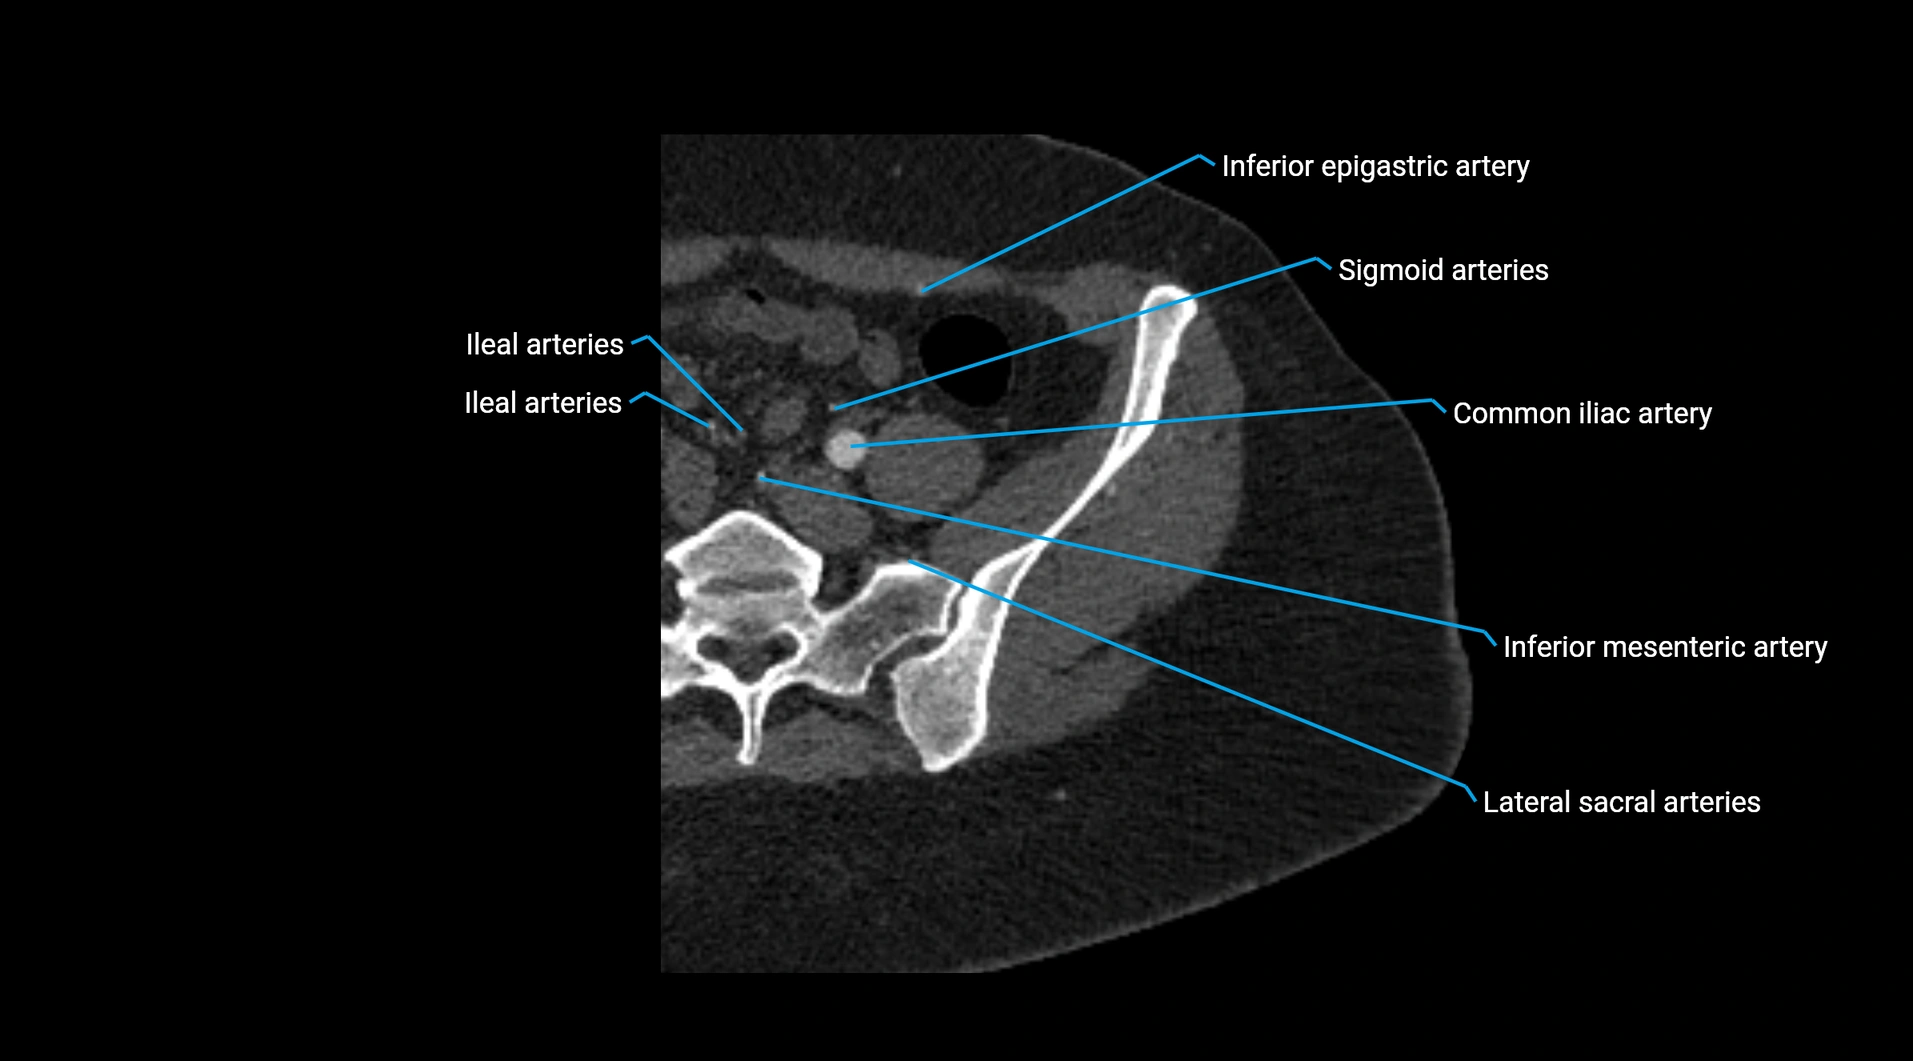

Contrast-enhanced CT (CTA):

• Gold standard for abdominal aortic imaging

• Provides excellent detail of lumen, wall, aneurysm, thrombus, and branch vessels

• Multiplanar and 3D reconstructions help in aneurysm measurement, stent graft planning, and dissection evaluation

• Detects acute rupture, traumatic injury, or occlusion with high sensitivity